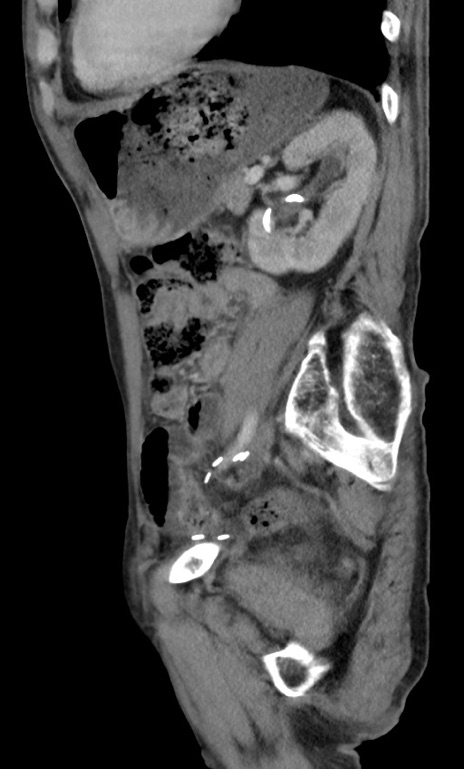

症例3(矢状断像)

【症例】 70歳代男性

【主訴】右鼠径部腫瘤、疼痛

【現病歴】本日朝より上記主訴あり、受診。

【既往歴】膀胱癌にて膀胱全摘、両側尿管皮膚瘻

【データ】WBC 5600、CRP 0.56